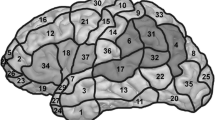

It has been shown that LI corresponds better with the Wada test if only language areas are used in the LI calculation [25, 26]. Therefore, the following regions of interest (ROIs) were defined: (1) Broca ROI, consisting of Brodmann’s area (BA) 44, BA45, and BA47; (2) Wernicke ROI, consisting of BA21, BA22, BA37, BA39, and BA40; and (3) combined ROI, including both the Broca ROI and the Wernicke ROI complemented with BA46, Heschl gyrus, and the hippocampus. The ROIs were defined using the atlases in WFU PickAtlas [27, 28].

The overall fMRI activation level varied not only between subjects, but also between tasks and analyses within subject. Figure 1 illustrates the group results of each task using the threshold of p < 0.05 (false discovery rate (FDR) corrected) and corresponding scatter plots of the sums of the T values and of the number of activated voxels (Fig. 1a, WGEN; Fig. 1b, RNAM; Fig. 1, c SCOMP; Fig. 1d, LET; Fig. 1e, WP). The mean and standard deviations of both of the sums of the T values and number of activated voxels are illustrated with an ellipse of radii of 2 × SD in each scatter plot in Fig. 1 and presented in Table 3. The standard deviation along the L = R line (SDact) represents the variation in total activation power and the standard deviation perpendicular to that (SDlat) represents the variation in laterality. When the tasks were examined separately, the RNAM produced the strongest activation (highest group mean in terms of both intensity and extent). The SDact was largest in the WP thus reducing the robustness of its activation power. The variation in laterality was smallest in the WGEN task and the SCOMP task had the smallest variation in total activation power. To be able to select tests to the optimal task battery, we used the criteria proposed by Binder [14]. Three tasks were chosen based on the robustness of the activation power and laterality, and capability to activate the language network as widely as possible: WGEN, RNAM, and SCOMP. Among the visual tasks, RNAM and WGEN produced both strong activations with clear left hemisphere lateralization. The LET task was excluded because of its poor activation power. The SCOMP task was selected as the auditory task since it produced much stronger activation with less variation than the WP task.

After comparing the five individual tasks, we performed comparisons between different combinations of tasks: (a) all tasks, (b) visual tasks, (c) auditory tasks, and (d) an optimal combination of visual and auditory tasks, i.e., WGEN, RNAM and SCOMP. Group results of activated areas in all four combination analyses are illustrated in Fig. 2 using the threshold of p < 0.05 (FDR corrected) along the similar scatter plots as for the single task analyses. The mean and standard deviations of the sums of the T values and of the number of activated voxels are illustrated with an ellipse of radii of 2 × SD in each scatter plot in Fig. 2 and further presented in Table 3. At the group level, the combination of all five tasks (Fig. 2a) and the combination of WGEN, RNAM, and SCOMP (Fig. 2d) produced almost identical results in terms of activated areas but the standard deviations SDlat and SDact were smaller in the combination of WGEN, RNAM, and SCOMP.